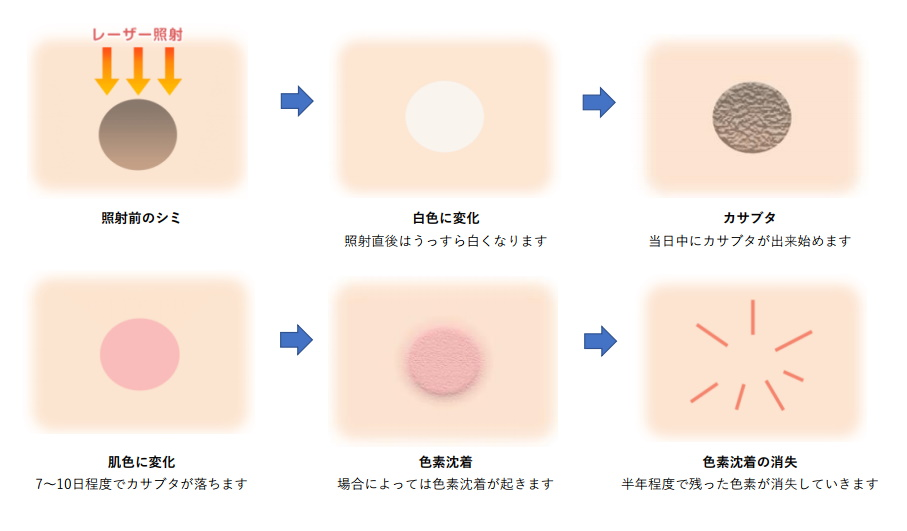

レーザーでシミ治療を行った1ヶ月後の経過 炎症後色素沈着- 東京・大阪の美容皮膚科ならFLALU フラルクリニック。

ほくろ除去後に茶色い跡が残るのはなぜ?色素沈着の原因と治し方 - 東京皮膚腫瘍ほくろと粉瘤クリニック 古林形成外科上野院。

シミのレーザー治療後の経過・炎症後色素沈着を検証してみたBeauty Tuning Clinic。

レーザー後の色素沈着例 ちゃんと改善クララビューティクリニック那覇院。